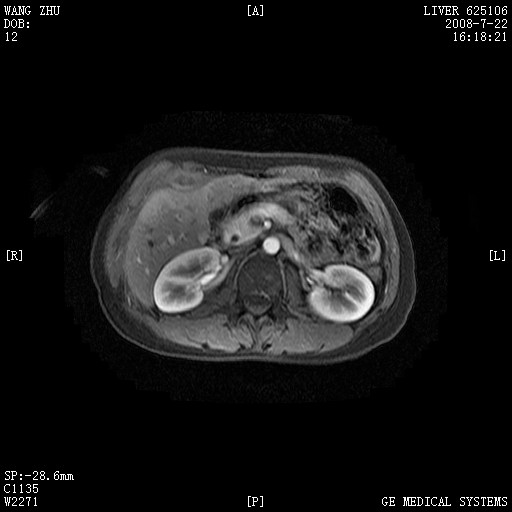

图像有点乱,病灶边缘清楚,可见纤维囊壁,灶旁可见异常灌注,增强显著增强,病灶有早期完全充填,无快退征像,考虑炎性病灶,肝结核可能性大,不知有何病史

肝前外缘见一类圆形囊性病灶,边缘强化,灶周肝为炎性渗出改变,其肝周可见少量腹水,符合炎性病变,病史较长---考虑腹膜结核。肝为外压性改变,脾为动脉期改变。

考虑血管瘤

考虑结核可能大一些

结核。

应该是肝结核。。这真是一个好病例